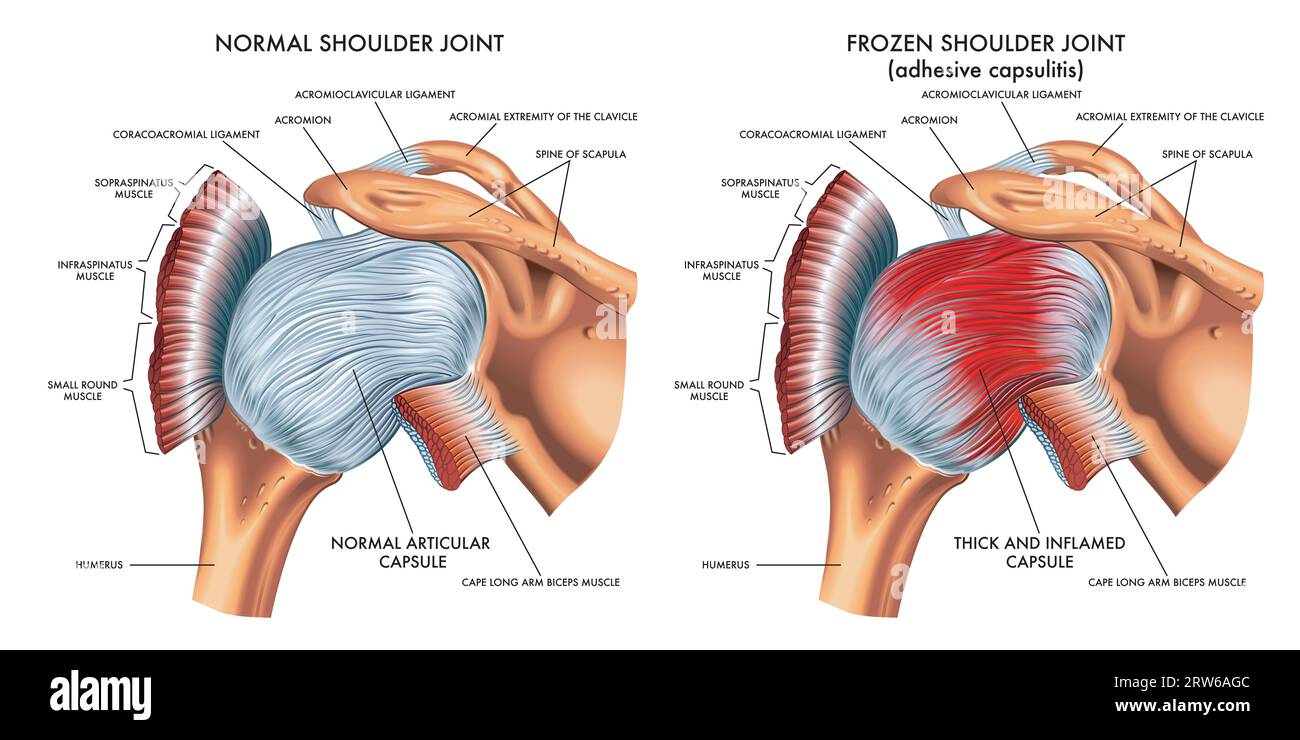

Medical illustration shows the difference between a normal shoulder joint and a frozen shoulder joint, with annotations. Stock Photohttps://www.alamy.com/image-license-details/?v=1https://www.alamy.com/medical-illustration-shows-the-difference-between-a-normal-shoulder-joint-and-a-frozen-shoulder-joint-with-annotations-image566238188.html

Medical illustration shows the difference between a normal shoulder joint and a frozen shoulder joint, with annotations. Stock Photohttps://www.alamy.com/image-license-details/?v=1https://www.alamy.com/medical-illustration-shows-the-difference-between-a-normal-shoulder-joint-and-a-frozen-shoulder-joint-with-annotations-image566238188.htmlRF2RW6AGC–Medical illustration shows the difference between a normal shoulder joint and a frozen shoulder joint, with annotations.